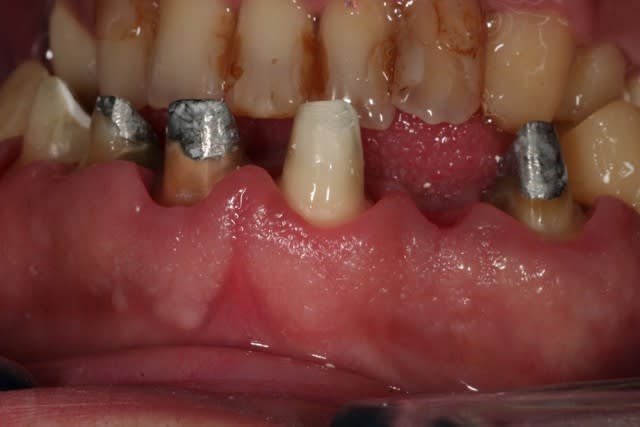

salut les petits clous...

voilà, je me suis remis un peu au boulot.

voici quelques images....

juste une remarque: pour l'instant je suis à la même DV.

et la suite...